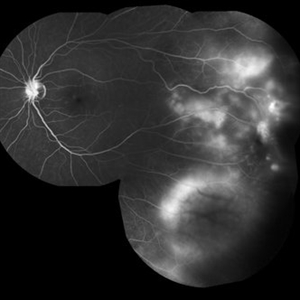

Central Retinal Vein Occlusion with Severe Ischemia

Composite fluorescein angiogram of the left eye of a male with a Central Retinal Vein Occlusion with severe ischemia.

Photographer: Olivia Rainey

Imaging device: Heidelberg Spectralis

Condition/keywords: central retinal vein occlusion (CRVO), composite, fluorescein leakage, ischemic CRVO